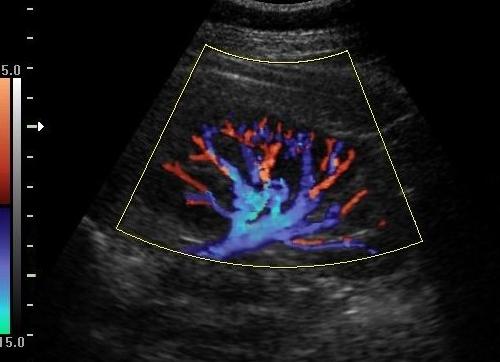

Так, одним из подвидов основного исследования является цветовое картирование, применяемое для обследования все тех же сосудов. На экране прибора появляется не черно-белое изображение, а различные цветовые оттенки, которые показывают картинку тока крови, его направленность, просвет и размер сосудов, а также сопротивление.

Допплерография сосудов (пример снимка)

ЦДК, или цветное допплеровское картирование, является совершенной методикой, которая позволяет совместить черно-белое УЗИ, при этом на мониторе у врача движение отдельных структур подается в цвете.

Красный цвет обозначает течение крови к датчику, голубой оттенок указывает на обратный кровоток. Ничего общего с условным обозначением вен (синим) и артерий (красным) получаемая на экране картинка не имеет.

ЦДК позволяет определять:

• направление тока крови;

• скорость;

• проходимость сосудов;

• особенности при изменениях кровотока;

• сопротивление;

• извитость;

• диаметр;

• утолщение или истончение.

Благодаря этому методу врач оценивает толщину сосуда, отсутствие или наличие бляшек при атеросклерозе, наличие извитых мест и аневризматического выпячивания.